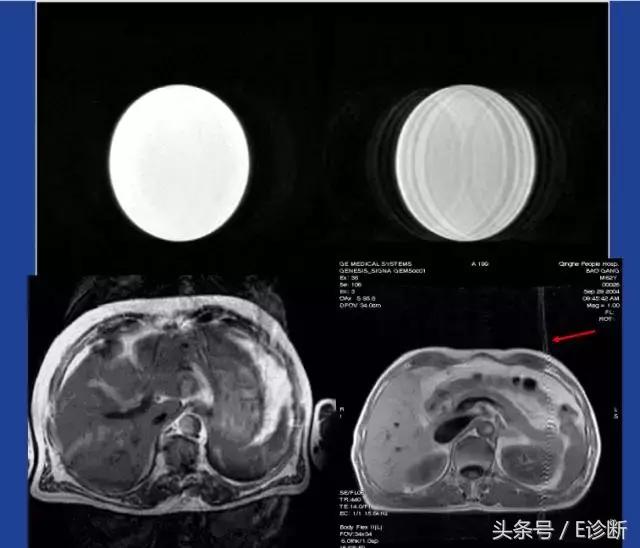

由于水和脂肪的振动频率不同,在一小段时间后,将出现水在脂肪前360°的相位。这时两者的自旋将处在完全相同的相位中。同样,在某一个时间点也可能出现两者180°相位差的情况。这种同相位和反相位的情况被称为II型化学位移伪影。

以1.5T为例,当TE=2.3时,正好处在水脂反相位的情况,当脂肪包绕的脏器周围将出现一条暗的边界(水信号和脂肪信号相减),称为钩边效应。

II型化学位移伪影在临床诊断中意义重大,对于细胞内含脂性病变(脂肪肝、肾上腺腺瘤)等的诊断非常重要。

图像处理伪影

对策:

1、升高带宽:以1.5T磁共振为例,当带宽为32kHz和256*256像素时,也即在x方向上覆盖整个图像长度的全部频率范围为32kHz,分为256等分。每个像素的频率范围为32kHz/256=125Hz。在脂肪和水中氢质子振动频率相差220Hz的情况下,两者的差异为2个像素。

如果升高带宽到64kHz,每个像素的频率范围将变成250Hz,这样水、脂的差异将变成1个像素的错误记录,从而降低化学位移伪影。但是升高带宽将降低图像信噪比。